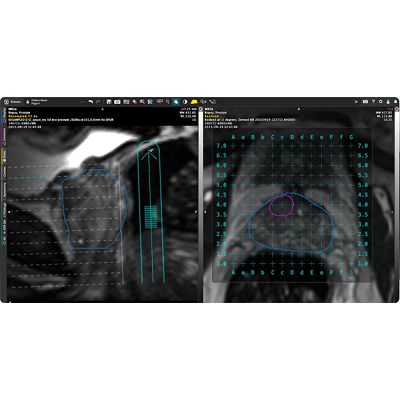

Brachytherapy Planning Using MR Fusion

MIM Symphony LDR allows for MR fusion and CT-based planning for prostate. It is a fully-featured solution without add-on modules.

Full treatment planning platform for MR or US-based planning with the same platform and tools as MIM Maestro®.

Easy review of customizable dose constraints on the user interface.

Unlimited number of dosimetric alerts.

Monitor dosimetric constraints based on prescribed parameters.

Acquire an active dose volume histogram (DVH) on any contoured structure within the 3D volume of the prostate.

DVH on any contoured structure within the 3D volume.